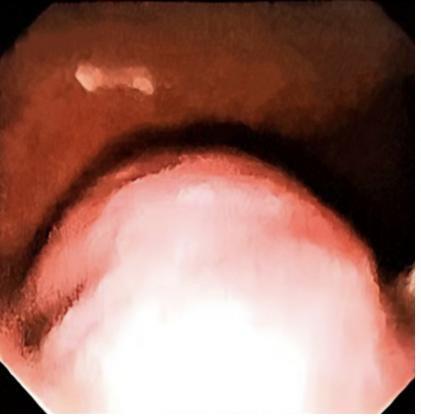

Switch/sucrose non-fermentable (SWI/SNF)-related matrix-associated actin-dependent regulator of chromatin subfamily B member 1 (SMARCB1)/integrase interactor 1 (INI1) (SMARCB1/INI1)-deficient undifferentiated pancreatic carcinoma (UPC) is an extremely rare special type of pancreatic cancer. This article reported the clinical manifestations, auxiliary examinations, diagnosis, and treatment of a patient with SMARCB1/INI1-deficient UPC, and reviewed the relevant literature. The patient, a 65-year-old female, was admitted due to intermittent upper abdominal pain for more than one month, aggravated with nausea and vomiting for 9 d. The abdominal CT scan performed at another hospital suggested a pancreatic space-occupying lesion. The physical examination results on admission revealed upper abdominal tenderness, without rebound tenderness or muscle guarding. The laboratory tests results showed a carbohydrate antigen 199 (CA199) level of 50.58 U·mL-1 and a fasting blood glucose level of 9.98 mmol·L-1. The abdominal MRI results revealed a mixed cystic and solid abnormal signal in the pancreatic body and tail, showing irregular extraluminal protrusion; it appeared as a slightly hypointense signal on T1-weighted imaging (T1WI), with the hemorrhagic part of the tumor appearing hyperintense; it appeared as a hyperintense signal on T2-weighted imaging (T2WI) with unclear boundaries, measuring 2.0-5.6 cm, causing compression and invasion of the gastric wall; enhanced scanning showed obvious rim enhancement of the tumor capsule, invasion of the splenic artery and vein, and portal vein thrombus formation. The gastroscope results revealed a 4.0 cm×5.0 cm mucosal elevation on the greater curvature of the gastric body, considered to be caused by compression from the pancreatic mass. The clinical diagnosis was a pancreatic space-occupying lesion, highly suspected to be malignant, with surgical resection being the preferred treatment option. The postoperative pathological diagnosis was SMARCB1/INI1-deficient UPC with a small component of moderately differentiated squamous cell carcinoma. The patient received chemotherapy after surgery and has been followed up for 5 months, with an improved quality of life compared to before surgery, no significant discomfort, and remains under close follow-up. SMARCB1/INI1-deficient UPC is relatively rare, with non?specific clinical manifestations, usually progressing rapidly and associated with a poor prognosis; therefore, early diagnosis and treatment should be pursued in clinical practice.